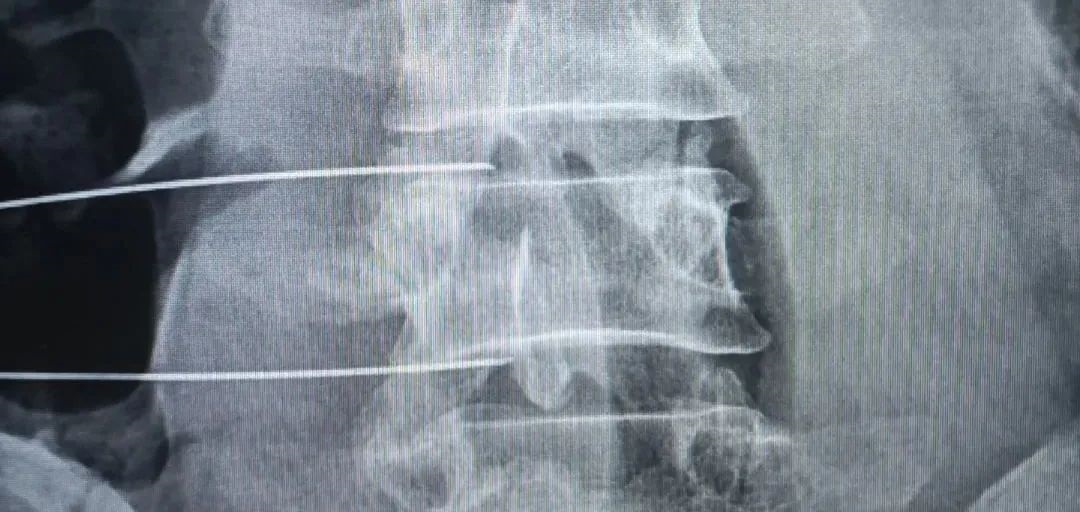

7月18日10时30分,手术室,骨科,医学影像科多学科联合,在数字胃肠机室行椎间盘介入射频消融术,术后症状立即得到缓解,郭老汉对治疗效果非常满意。

频消融术是将0.4mm电极针作用于患者突出的椎间盘髓核或病变的纤维环周围,利用温控方法进行热凝毁损,使突出的髓核变形、凝固、收缩、减小体积,从而解除对神经根的压迫达到根治的目的。